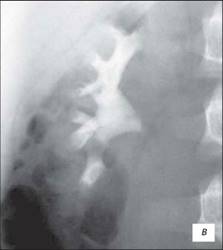

Висхідна цистографія

На даній рентгенограмі спостерігаємо активно-пасивний міхурово-сечовий рефлюкс зліва 4 ступені. Виражена дилатація чашечко-мисочкової системи, деформація чашок.

а – у фазі максимального наповнення сечового міхура, пасивний рефлекс;б – у фазі сечовипускання, активний рефлекс.